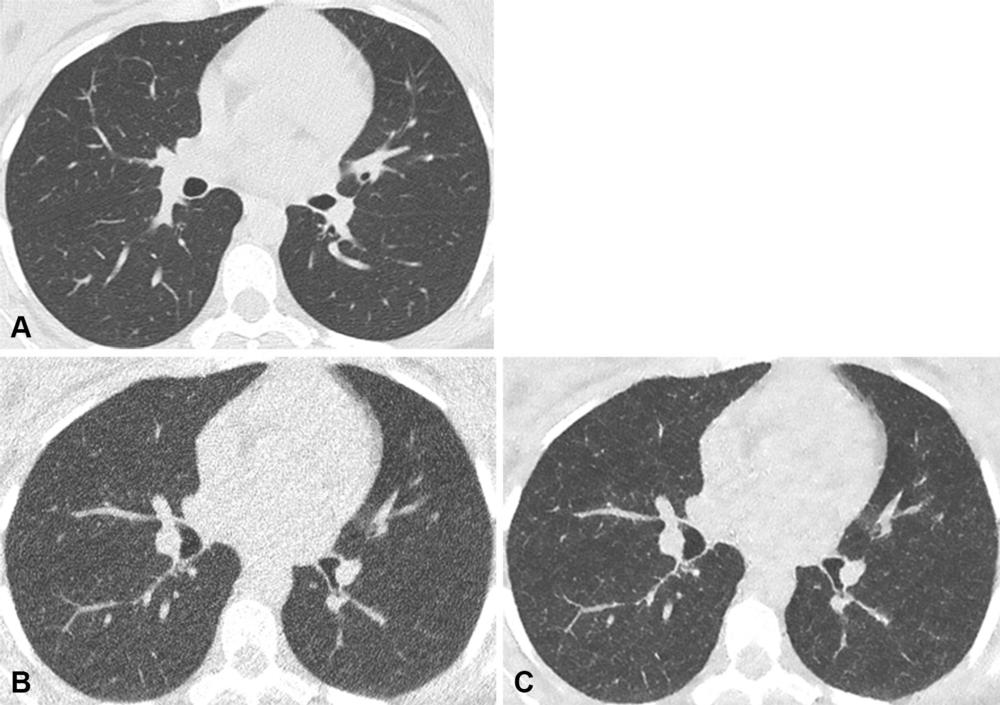

Figure 2. Axial noncontrast chest CT lung window images in a 42-year-old male participant with normal lungs. (A) Normal-dose CT, (B) ultra-low-dose CT (ULDCT), and (C) denoised ULDCT images. Normal lungs were observed on normal-dose CT image. However, due to inherent image noise at ULDCT, the lung pattern was falsely classified as positive viral infection by both readers. The denoising technique of the denoised ULDCT corrected this artifact, and the participant was correctly categorized as having no infection.

Figure 3. Axial noncontrast chest CT lung window images in a 54-year-old female participant. (A) Normal-dose CT, (B) ultra-low-dose CT (ULDCT), and (C) denoised ULDCT images show a solid lung small nodule of less than 1 cm (yellow arrow). A solid nodule was observed on normal-dose CT image. However, image noise at ULDCT precluded the correct classification, and the nodule was identified as part solid by both readers. Denoised ULDCT reduced the image noise, allowing correct classification as a solid nodule.